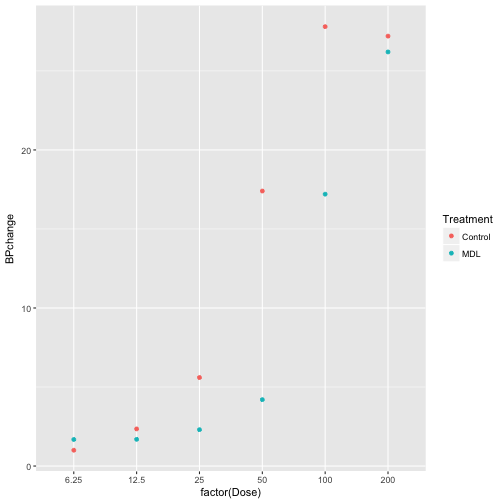

# use stat_summary function to generate mean for each BPchange per Dose

p +

stat_summary(geom = 'point', fun.y = mean)